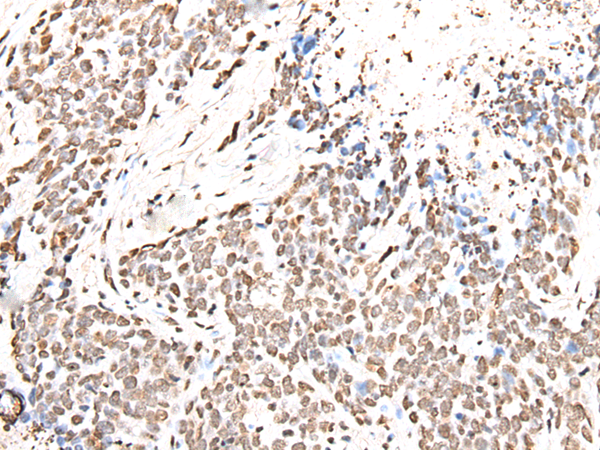

分类: 科研抗体货号: P05809别名: MCT6; MCT7应用: WB,IHC反应种属: Human